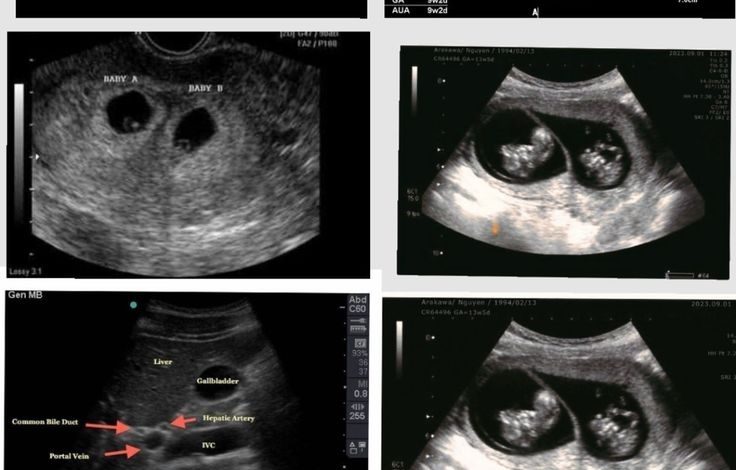

جاءت الصدمة للزوجين خلال جلسة تصوير بالموجات فوق الصوتية (سونار) روتينية، حيث أظهر الجهاز وجود تسعة أكياس حمل تحتوي على أجنة في مراحلها المبكرة، مما حوّل لحظة الفرح المعتادة إلى دهشة كبيرة للأسرة والطاقم الطبي.